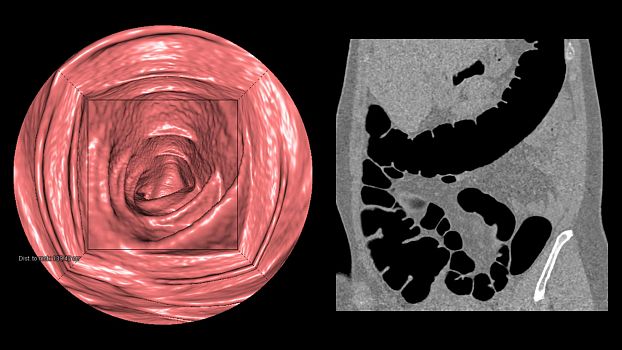

Клинические изображения

- Опциональные возможности — ангиография, виртуальная колоноскопия, технология скопии

- Опциональные возможности — ангиография, виртуальная колоноскопия, технология скопии

SOMATOM go.Up позволяет проводить скрининговые исследования лёгких и толстой кишки, а также исследования сердца для оценки коронарного кальция. Благодаря субмиллиметровой коллимации SOMATOM go.Up обеспечивает высокое пространственное разрешение, тем самым повышая чувствительность диагностики в онкологии.